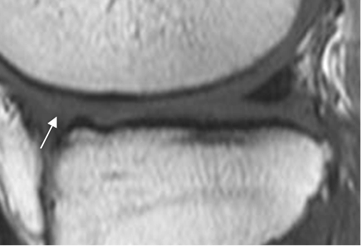

Fig 68. Ruptura meniscal dudosa.

A y B: RM sagital en T1. Imágenes hiperintensas y en sentido oblicuo, sobre el cuerno posterior del menisco interno. La completa comunicación con el borde inferior, es difícil de determinar con certeza.